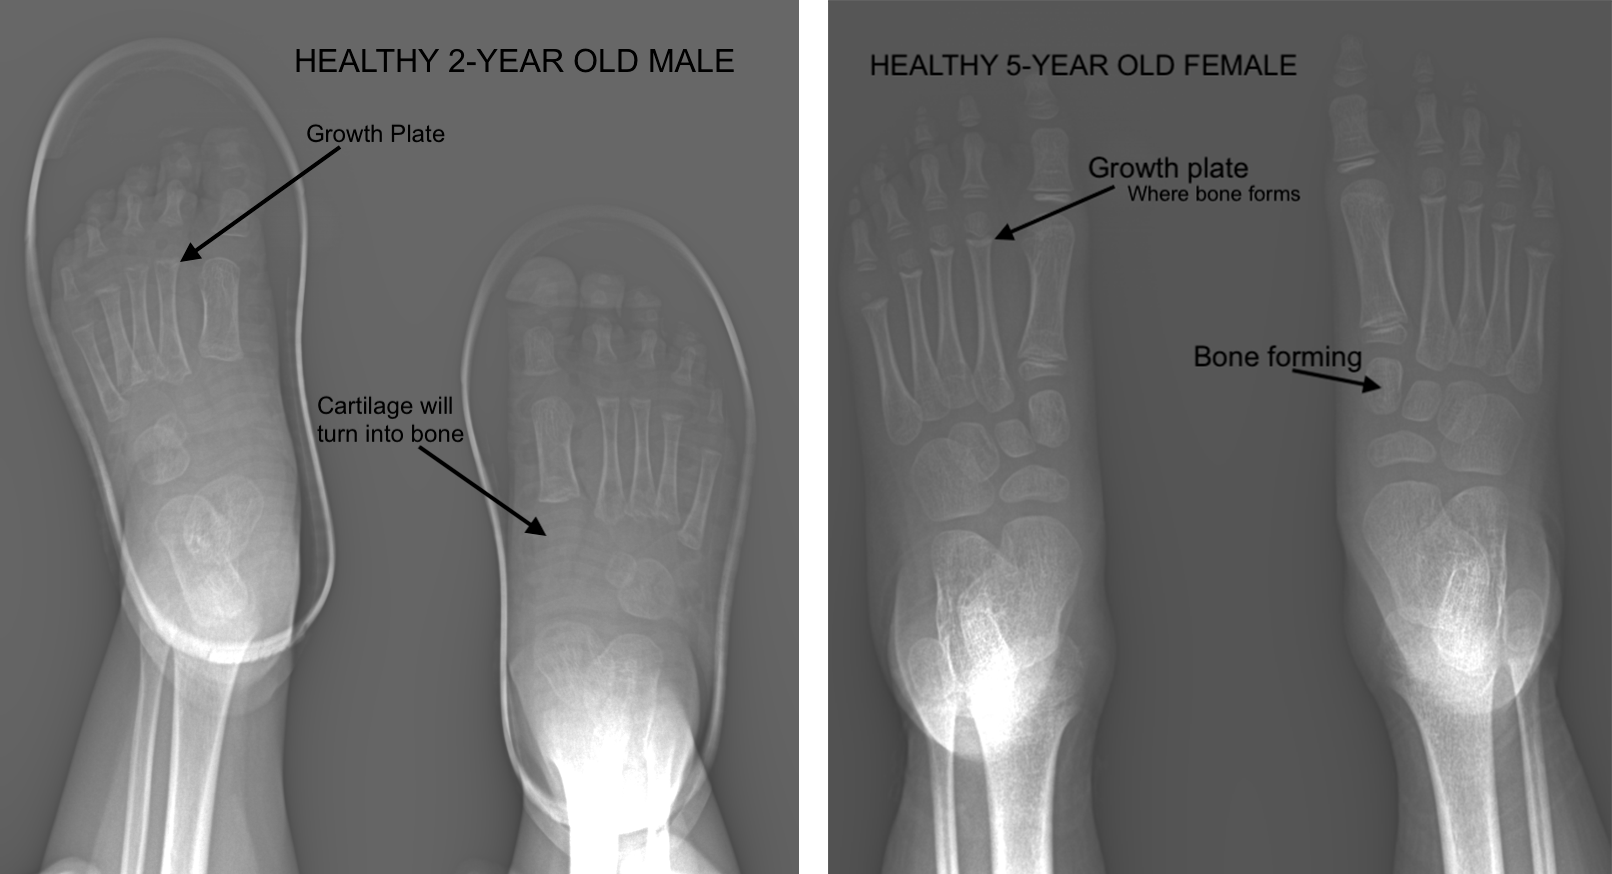

Is it true that a picture says 1,000 words. In the case of an x-ray, YEP! In-office x-ray is very helpful to assess fractures, foreign bodies, clogged arteries, arthritis, and growth plate patterns and injuries. It is important to get this real-time picture for a most accurate picture of what is actively going on inside your feet and ankles. Even a few days can make a big difference in images, so doing an x-ray in our office at the time of your appointment is the most accurate to the diagnostic process.

In children, we want to see a healthy growth plates, cartilage (as opposed to bone) and healthy tendons and ligaments to understand if they are growing at a steady rate. X-rays help us determine how to design an orthotic around a foot type to help prevent or relieve pain in the natural aging process, determine if a fracture needs surgery, if its a broken bone or arthritis causing pain.